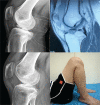

Arthroscopic techniques are considered the gold standard for treatment of displaced avulsion fractures of the anterior cruciate ligament. However, most arthroscopic surgical techniques and fixation methods are technically demanding and require removal of hard implant. This report describes a new, easy, safe, and all-arthroscopic method for reduction and fixation of displaced tibial intercondylar eminence fractures by using 1 anchor and 1 Pushlock.From January 2015 to June 2017, 8 adult patients with type II and III displaced tibial intercondylar eminence fractures were operated using this technique. Clinical assessment included patient demographics, cause of injury, delay before surgery, operation time, time to return to work and sport, International Knee Documentation Committee scores, and Lysholm knee scores.The average operation time was 48 minutes. The average follow-up period was 12.5 months. At the 6-month follow-up, all patients had acquired fracture union and complete functional recovery and were able to return to work. International Knee Documentation Committee objective scores and Lysholm knee scores were 92.4 (range 88-94) and 93.6 (range 90-96), respectively. At the last follow-up, anterior drawer, Lachman's test, and pivot shift tests were negative, and all patients had returned to their preinjury activity levels.Arthroscopic fixation by use of 1 anchor and 1 Pushlock is an easy, safe, and minimally invasive technique for treatment of displaced tibial intercondylar eminence fractures and does not require further surgery to remove fixation devices.Level of Evidence: Level IV, therapeutic case series.